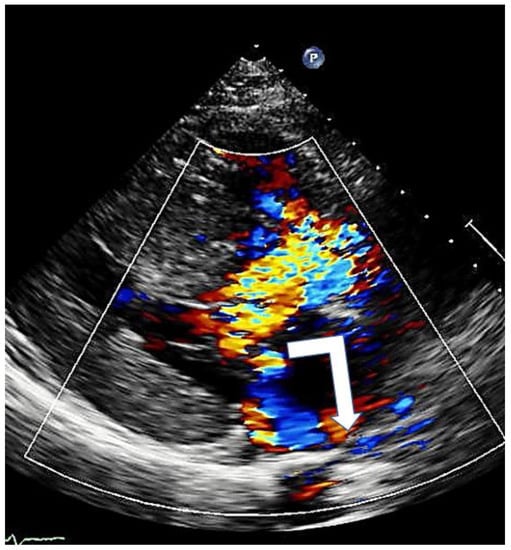

Color Doppler echocardiography identifies the presence and degree of mitral regurgitation and helps to understand the level at which obstruction occurs.

Mitral regurgitation (MR), caused by SAM, is observed in almost all patients with HOCM anterior mitral leaflet elongation and the associated increased mobility impairs adequate leaflet coaptation, resulting in SAM-related, eccentric posterior and lateral MR (Figure 6). When additional mitral valve abnormalities other than SAM are not observed, a direct relation between the pressure gradient and the severity of MR is evident. A central or anterior jet often indicates the presence of organic mitral valve disease [17].

Figure 6. Mitral regurgitation in hypertrophic cardiomyopathy due to systolic anterior motion of the mitral valve; typical eccentric posterior direction (arrow).